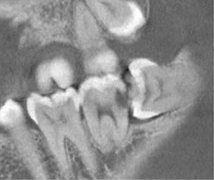

実際のCT画像

このCT画像は実際に親知らずが横向きに生えていることによって、手前の歯が虫歯になってしまっている様子です。こういった症例の場合は、親知らずの抜歯を行ったうえで手前の歯の虫歯治療を行う必要があります。